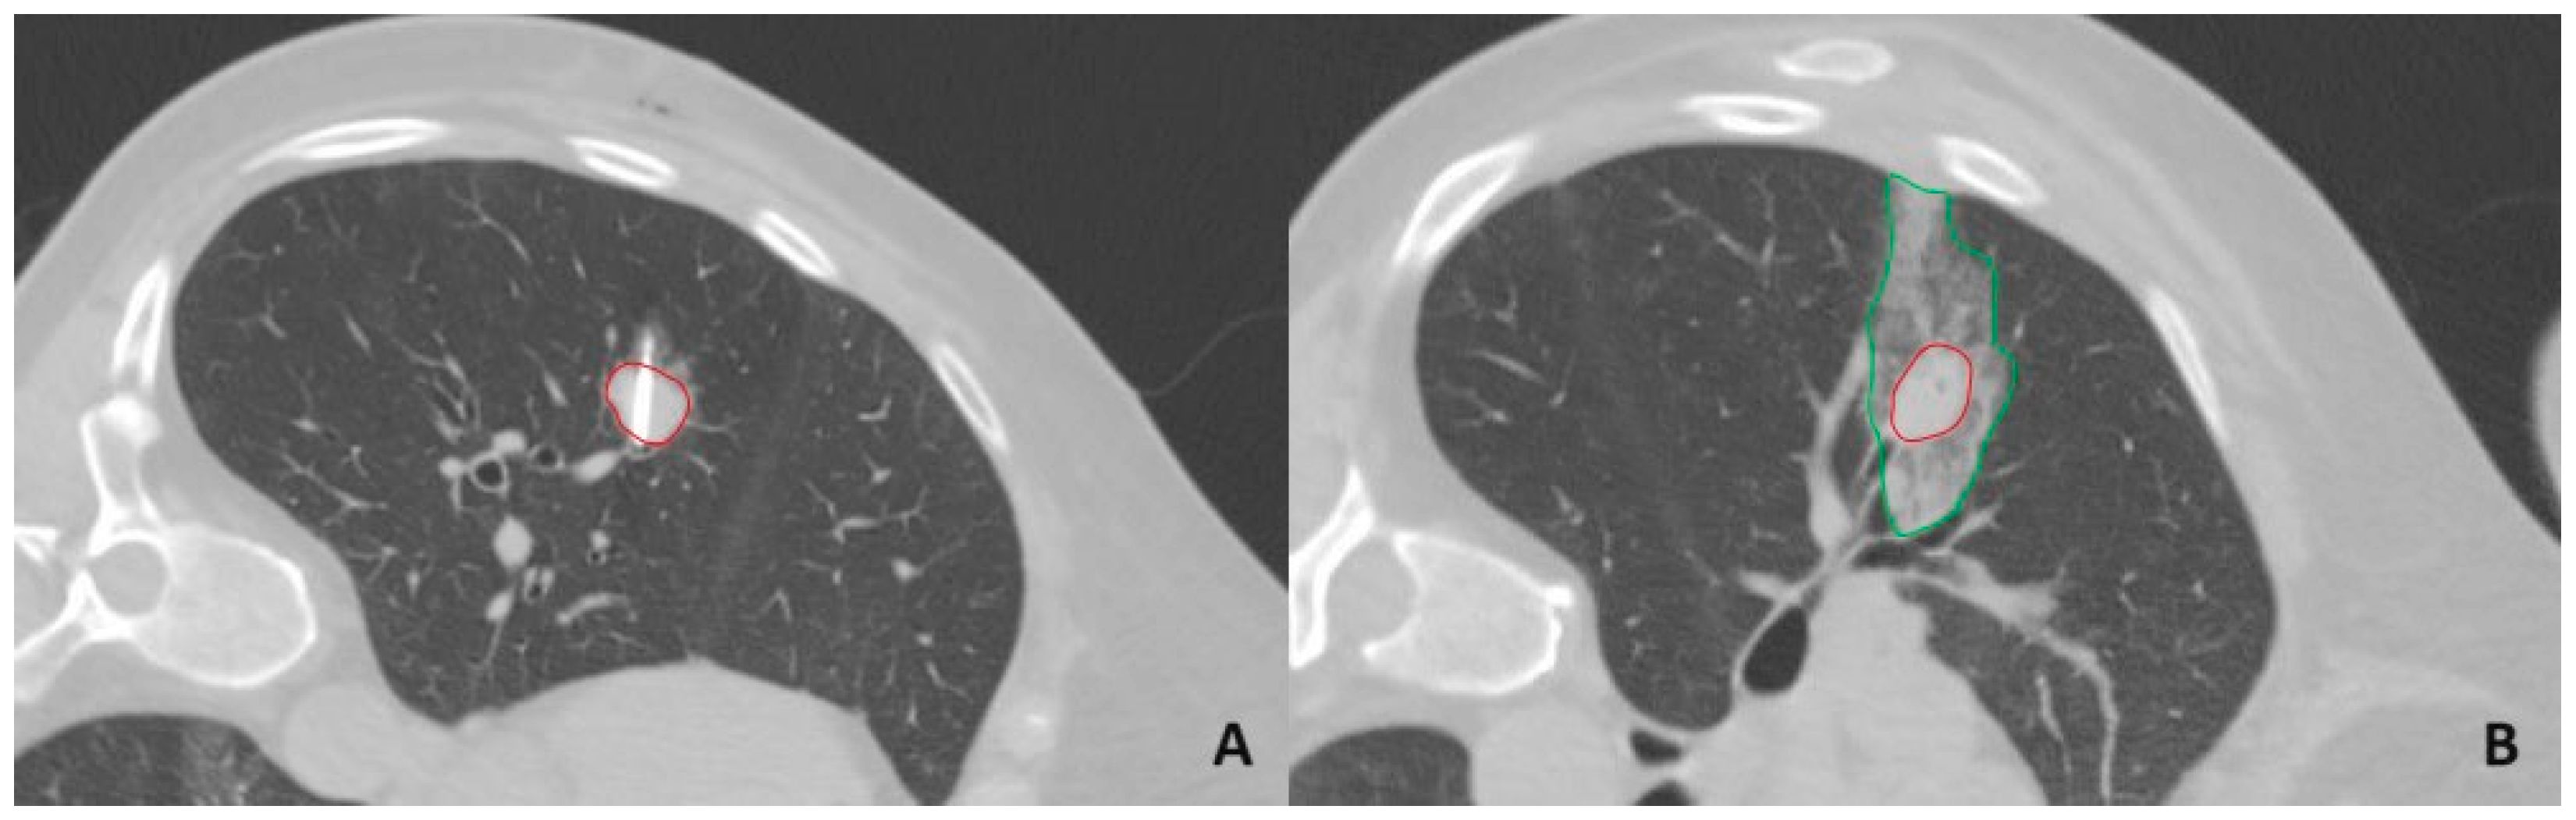

1. Introduction

2. Materials and Methods

2.2. Microwave Ablation Procedure

2.3. Tract Sealing Using an Autologous Venous Blood Clot